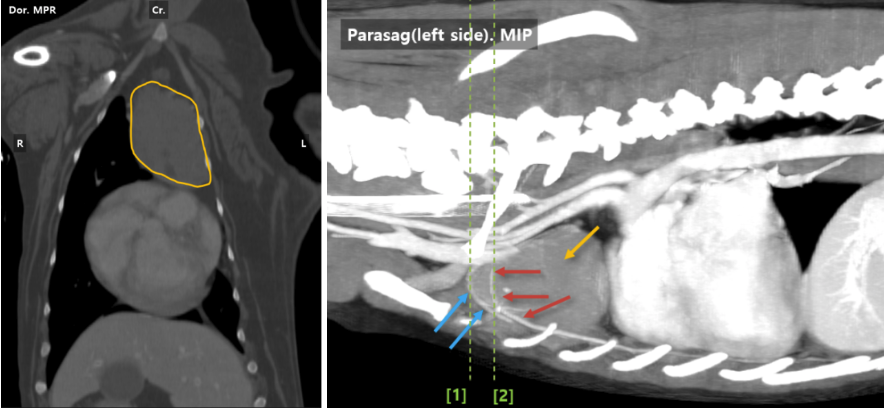

■ 흉부 CT 검사 결과

종격동 공간 내 흉선에서 유래한 흉선종양이 진단되었으며, 다른 장기로의 전이는 확인되지 않았습니다.

강아지 흉선 종양 CT 검사 결과/ 출처: 에스동물메디컬센터